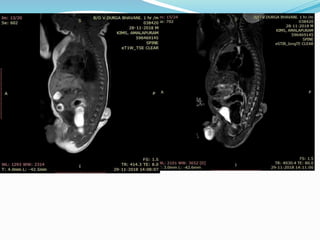

Type 1 diastematomyelia. Sagittal T2-weighted MR (A), axial T2-

weighted MR (B), and axial CT with bone algorithm (C) images in 6-

year-old boy show two dural tubes separated by osseous bridge

(arrows), which is characteristic for type 1 diastematomyelia